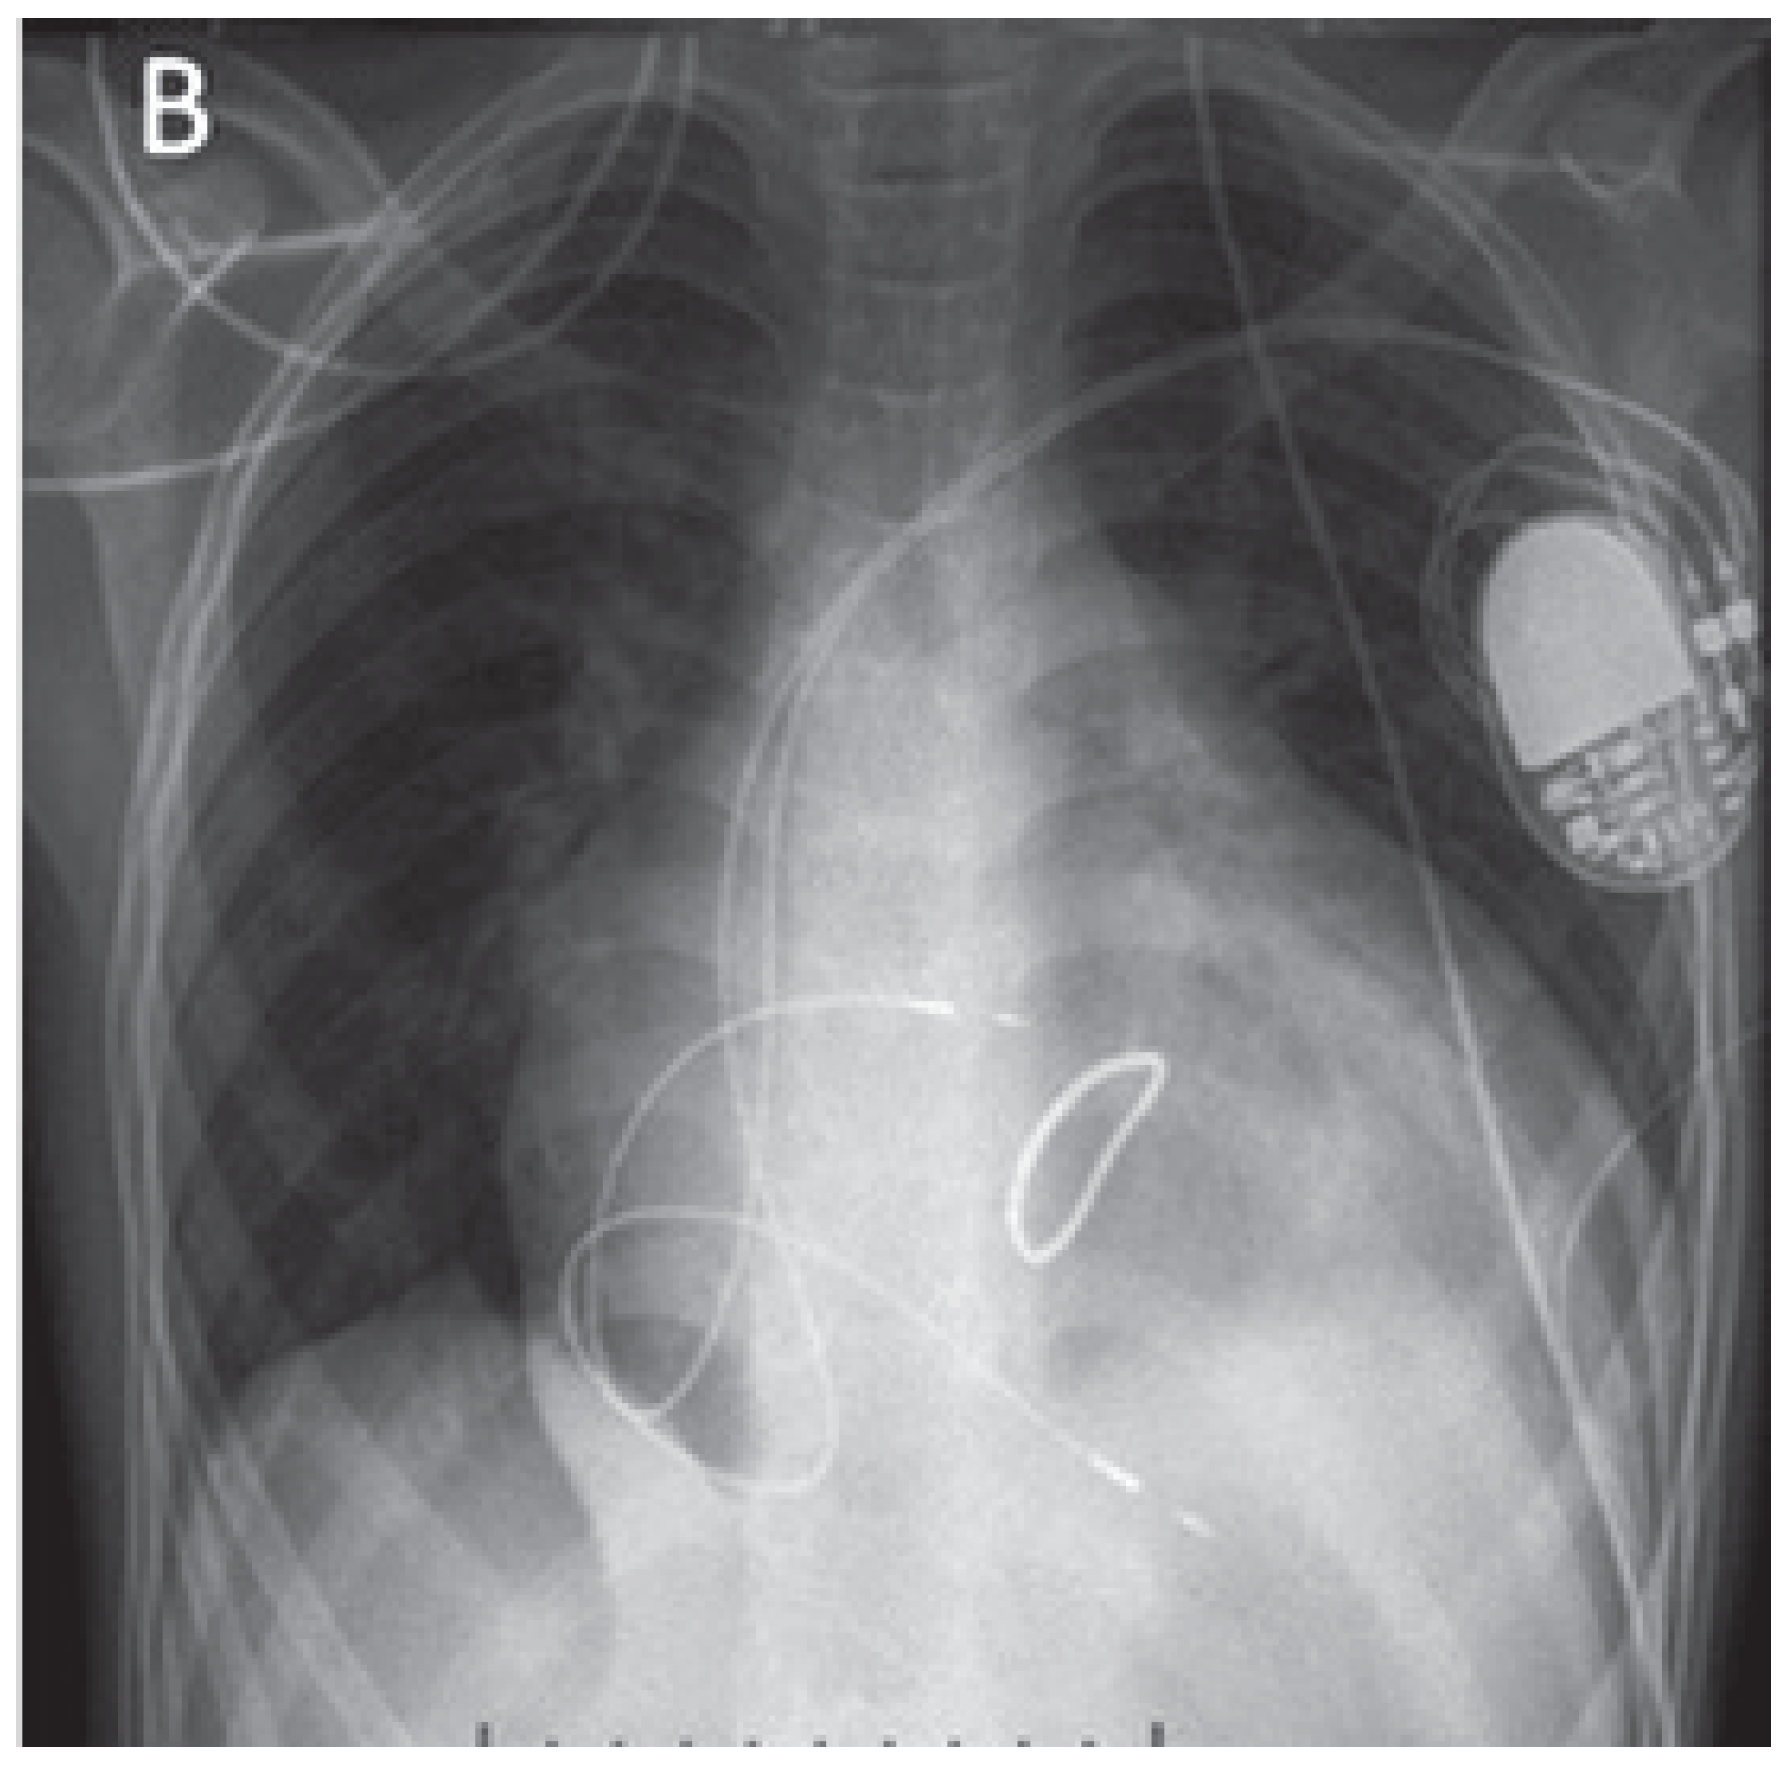

Figure 3. Final position of SelectSecure 3830 leads positioned in the right atrium and right ventricle, with loops to accommodate for future growth. Image from patient 9 (age 14 yr, weight 32.4 kg, height 154 cm).